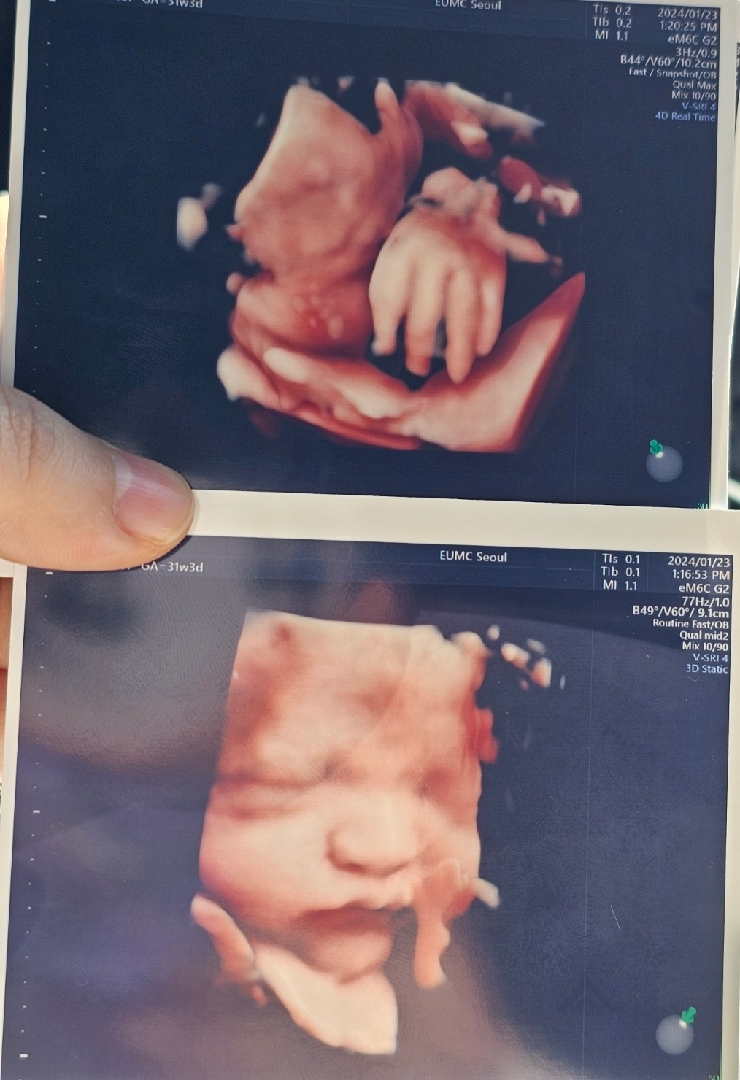

애기가 잘 돌았데요! 31주 진료후기

31주 3일 1.7키로 딱 평균 28주에 역아였는데 잘 돌아서 머리가 밑으로 왔어요 역아체조는 한두번 밖에 못했는데 ㅋㅋㅋ 알아서 잘 돌아줘서 너무 기특해요 효자네요 효자 그래서 자연분만도 된다는데 제가 선택제왕 말씀드려서 날짜도 3.15일로 잡았어요 ㅋㅋ 예정일은 3.23인데 사주나 철학관은 안보고 그냥 교수님 수술 가능한게 13 15인데 13일보다 15일이 어감이 좋아서? 아무 문제 없어서 다음 진료는 3주 뒤로 잡았고 그 때 산전검사 한다네요 그리고 진짜... 크면 클수록 남편이랑 똑같이 생겨서 상대적 박탈감?! 을 느끼고 있어요 ㅋㅋㅋㅋ 눈 코 입 다 남편닮았네요 진짜 씨도둑은 못하나봐요 이제 체중만 좀 더 안찌게... 관리하고 하면 될거 같아요 숨차고 계단 못올라가고 둔해지고 잘때 다리도 저리지만 애가 건강하다니 다 괜찮아요 ㅎㅎ 이게 모성애인가

두번째 아가사진 너어무 잘 나왔네요 귀엽귀엽^^ 저희아가는 얼굴옆에 손 두는게 좋은가봐요😅

ㅋㅋㅋ 교수님이 손을 초음파 포토샵같은걸로 지워주셨어요 얼굴은 손에 모으는게 태아들 트렌드인가봐요

볼살 오동통해서 너무너무 귀여워요ㅠㅠ 출산까지 화이팅입니당!